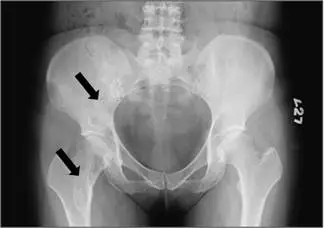

51 歲女性病人主訴右髖關節疼痛約 3週,附圖為骨盆 X光片,箭號所指處最可能的診斷為: 圖片

骨盆正位 X 光顯示左側髂骨及股骨近端(含股骨頸部位)有兩個箭號標示之病灶。病灶呈現以下特徵:

• 密度:呈現典型的「毛玻璃樣(ground-glass)」密度,均勻、略高於正常骨髓但低於皮質骨,為纖維性骨異生的標誌性表現

• 邊界:邊緣清楚,有硬化性邊界(rind sign),代表反應性骨形成包覆病灶

• 骨皮質:骨皮質完整,無破壞或穿透,無骨膜反應(periosteal reaction)

• 軟組織:無軟組織腫塊延伸

• 位置:病灶位於髂骨及股骨近端,屬於纖維性骨異生好發部位

• 骨骼變形:股骨近端可見輕度變形,符合纖維性骨異生因反覆承重導致變形的特性

上述影像特徵(毛玻璃密度 + 邊界清楚 + 無骨膜反應 + 無軟組織侵犯)高度符合纖維性骨異生的典型表現。

(A) fibrous dysplasia(纖維性骨異生) 正確答案。51 歲女性,右髖疼痛約 3 週(慢性病程)。X 光顯示骨盆左側骨骼病灶呈現毛玻璃樣密度,邊界清楚